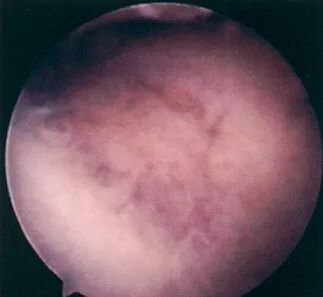

病理分级

关节镜下可将髌骨软化分为5级:

0级:正常关节软骨

Ⅰ级:关节软骨失去珍珠样外观而变得较暗淡,局部软化,肿胀区或纤毛化区的直径<0.5cm。

Ⅱ级:关节软骨软化区内出现毛刷状或纤毛化改变,深达1~2mm,直径≤1.3cm。

Ⅲ级:软骨的毛刷状或纤毛化改变达关节软骨厚度一半以上,直径>1.3cm,关节软骨表面类似蟹肉样改变,表面有多发软骨碎片附着其下的软骨。

Ⅳ级:关节软骨全层受侵,软骨下骨暴露,表现为进展期髌股关节炎。

Ⅰ~Ⅱ级为早期,主要保守治疗。

Ⅲ~Ⅳ级为进展期,需手术及关节镜治疗。

• 关节镜:是髌骨软化症确诊与治疗的有效手段之一,可以在镜下直接观察软骨面的变化,但不能够观察到软骨下骨的变化